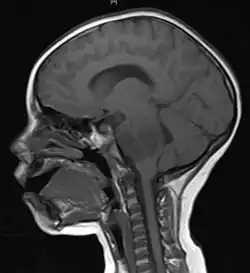

A brainstem glioma in four-year-old. MRI, sagittal, without contrast

Led by Prof. Nori Kasahara, researchers from USC, who are now at UCLA, reported in 2001 the first successful example of applying the use of retroviral replicating vectors towards transducing cell lines derived from solid tumors.[113] Building on this initial work, the researchers applied the technology to in vivo models of cancer and in 2005 reported a long-term survival benefit in an experimental brain tumor animal model.[114] Subsequently, in preparation for human clinical trials, this technology was further developed by Tocagen (a pharmaceutical company primarily focused on brain cancer treatments) as a combination treatment (Toca 511 & Toca FC). This has been under investigation since 2010 in a Phase I/II clinical trial for the potential treatment of recurrent high-grade glioma including glioblastoma and anaplastic astrocytoma. No results have yet been published.[115]